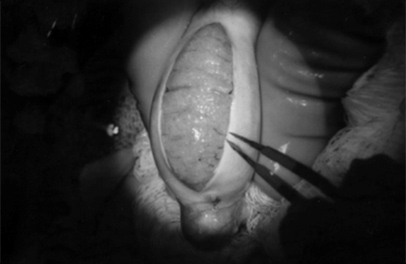

ń¼¼õ║īõ╗ŻĶ»Ģń«ĪÕ®┤Õä┐’╝ÜÕŹĄń╗åĶā×µĄåÕåģÕŹĢń▓ŠÕŁÉµśŠÕŠ«µ│©Õ░äµēŗĶē║